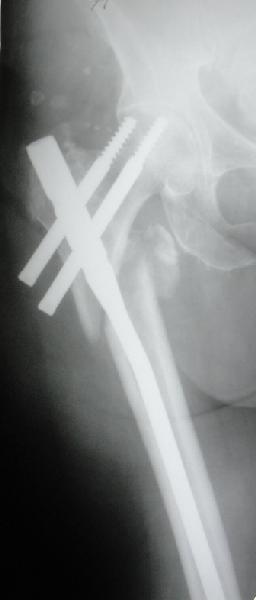

До выхода блокируемых гвоздей для фиксации косых подвертельных переломов в основном применяли Blade Plate. За счет уникальной конструкции создавался Fixed Angled Device, который соединял головку с диафизом, минуя зону перелома.

За счет особой конструкции клинка и подпорки (buttress) в диафиз создавалась стабильность, и предупреждалось скольжение по линии перелома. Перпендикулярная поверхность клинка предупреждала сгибательные и разгибательные смещения, и в сравнении с круглым винтом редко происходило прорезыванием.

Первые реконструкционные гвозди без блокировки винтов не смогли повторить преимущества, и из-за Z эффекта винтов происходило быстрое расшатывание.

С приходом менее агрессивных блокируемых цефаломедуллярных гвоздей (Gamma 3 и другие) изменилась тактика лечения. Несмотря на то, что вся стабильность держится вокруг одного блокирующего винта, в большинстве случаев гвозди приводили к успеху.

В данном случае в головке бедра и в вертлужной впадине огромный дефект, навряд ли удалением импланта или заменой на другой можно сохранить сустав.

Вашему вниманию представляется похожий случай, пациентке 70, осложнился в течение одного месяца после операции. Ревизия с заменой сустава, кабельная фиксация на трохантер. При установке в дистальном диафизе обнаружен тонкий кортикальный слой и сделана профилактика от возможного перелома аллографтом.